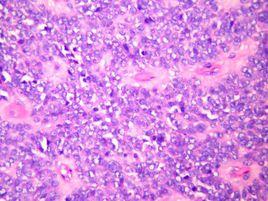

在多發性肌炎(PM)中陽性率達25%左右。在皮肌炎(DM)中陽性率為7.1%。合併肺間質病變的PM/DM患者,陽性率高達60%。

67%抗Jo-1抗體陽性的患者有HLA-DR3抗原。其他結締組織病為陰性。在抗JO-1和抗SSA二項陽性,約80%的多發性肌炎和皮肝炎患者合併有乾燥綜合徵。而抗JO-1與抗RNP兩項陽性者臨床上都發現有雷諾氏現象。抗Jo-1抗體綜合徵:抗Jo-1抗體陽性、急性發熱、對稱性關節炎、技工手、雷諾現象、肌炎、肺間質病變。